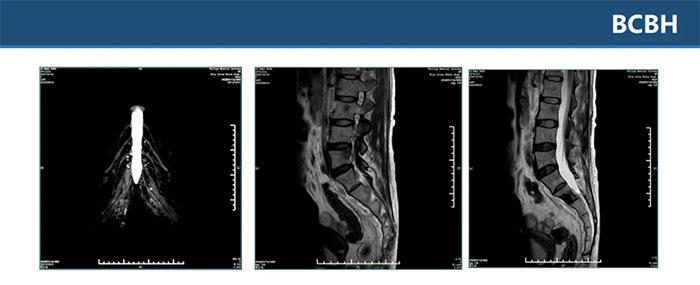

▲ 双侧骶丛神经平扫+增强未见明显异常,L2、L4、骶S1-3椎体及其附件区多发异常信号影